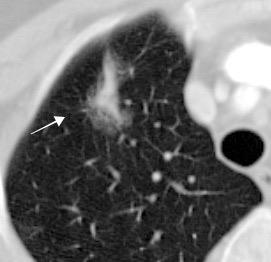

BRONQUIO POSITIVO SIGNO DEL Positive bronchus sign

Un bronquio con aire que termina abruptamente en una masa o nódulo periférico.

Frecuentemente visto en carcinoma con crecimiento lepídico y adenocarcinoma

Chiarenza et al. Chest imaging using signs, symbols, and naturalistic images: a practical guide for radiologists and non-radiologists. Insights into Imaging. 2019.

Anantham EA. Bronchus sign on CT scan rediscovered. Chest 2010

LM : Adenoca. predominantemente acinar. Tiene un 2º en LSD.

Adenocarcinoma de crecimiento lepídico

BRONQUIO POSITIVO. SIGNO DEL

Positive bronchus sign

Un bronquio con aire que termina abruptamente en una densidad periférica.

Las lesiones inflamatorias crónicas como Tb pueden presentar engrosamiento de las paredes de un bronquio que remeda este signo. (“bronquio de drenaje”).

El broncograma puede prolongarse dentro de la lesión

Absceso pulmonar por Rothia mucilaginosa.(saprofito habitual). Gram+,